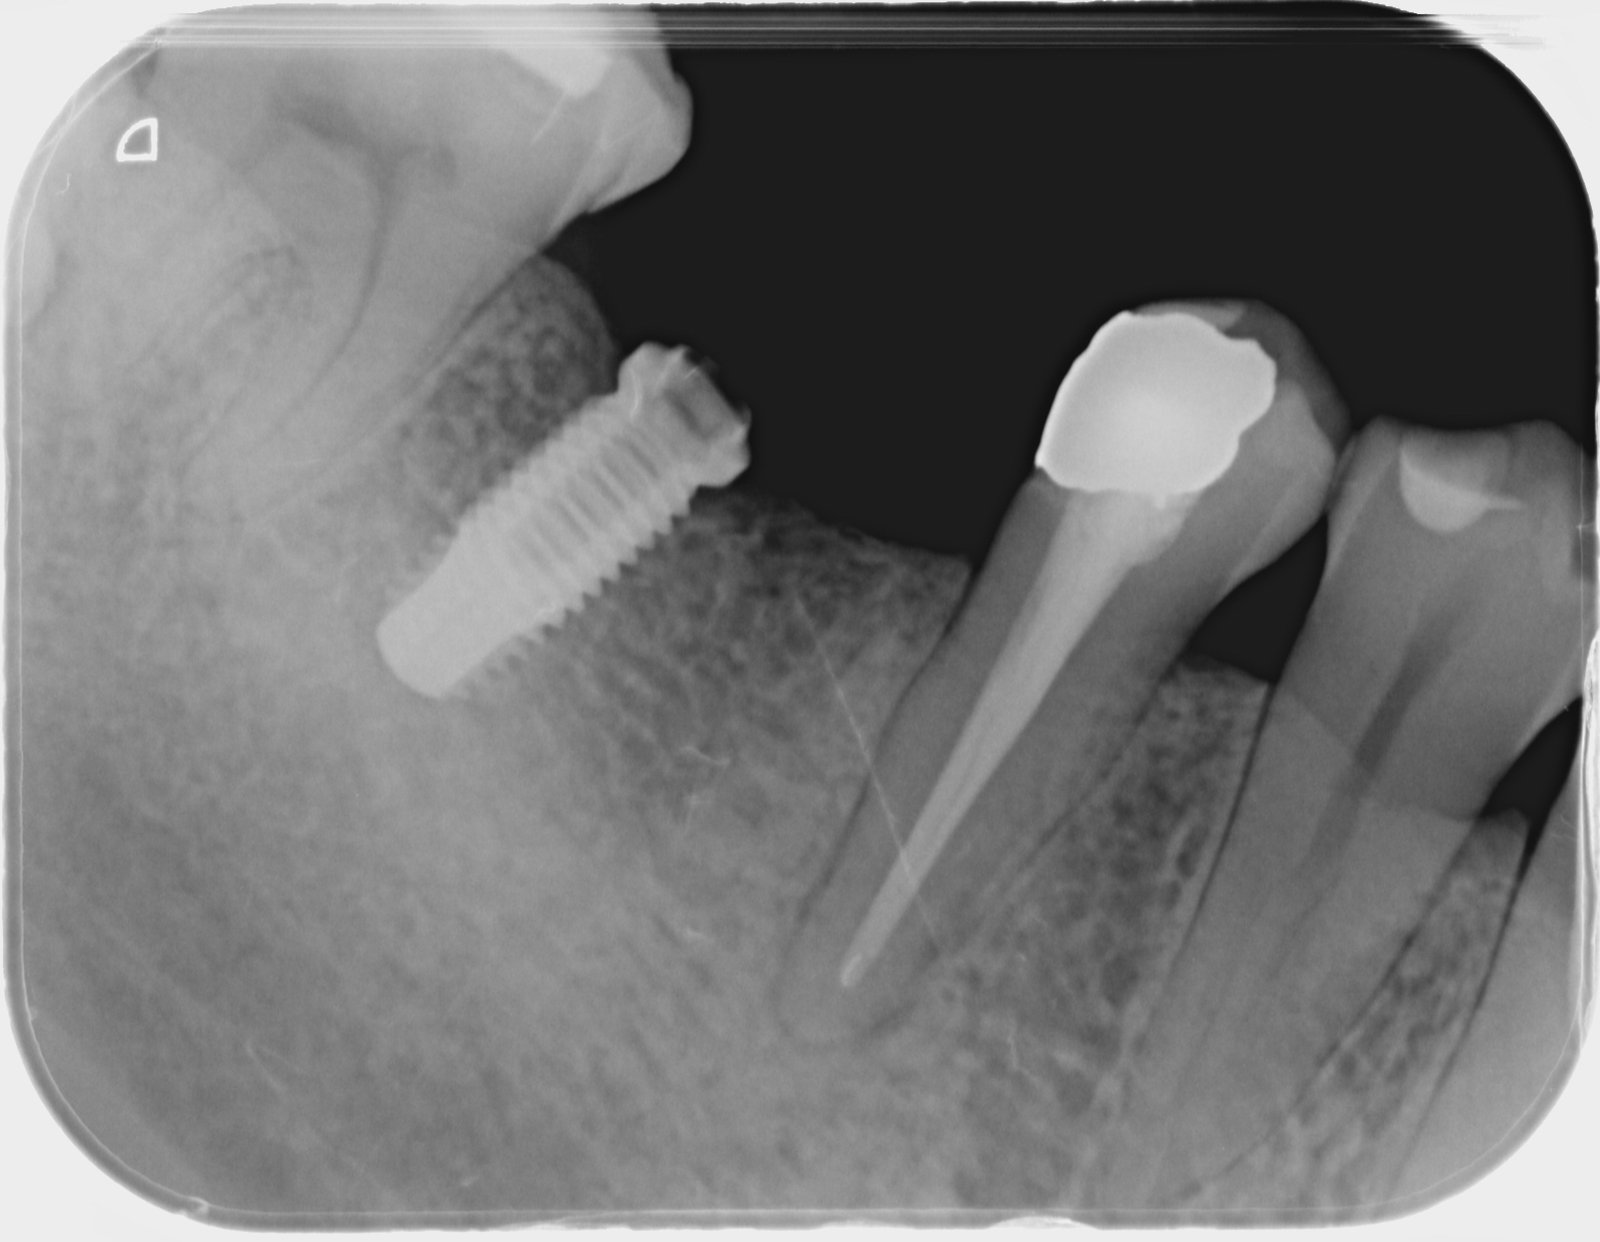

No se que implante y conexiones compatibles puedo utilizar para reponer la corona.

Se trata de un implante de conexión interna colocado hace mas de 20 años nos comenta el paciente.